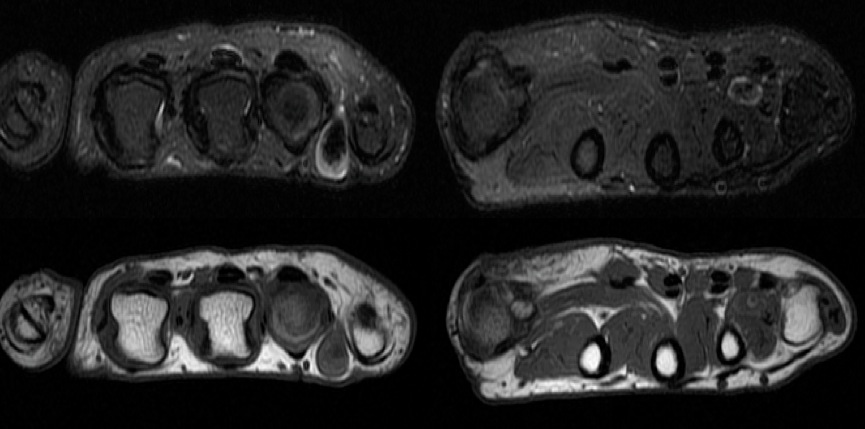

Figure 2 for case Venous malformation ( RID3337 )

Figure 2